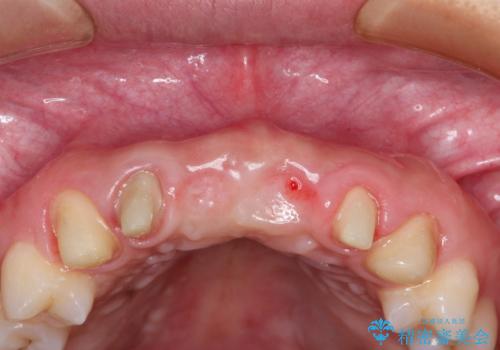

- 数ヶ月前に治療終了したブリッジの歯ぐきの違和感が強く、改善を求めて来院されました。

歯ぐきは著しく腫れ、少し触ると出血してしまうような状態であったためブリッジの再作製・歯周外科を用いた歯肉環境の改善を計画します。